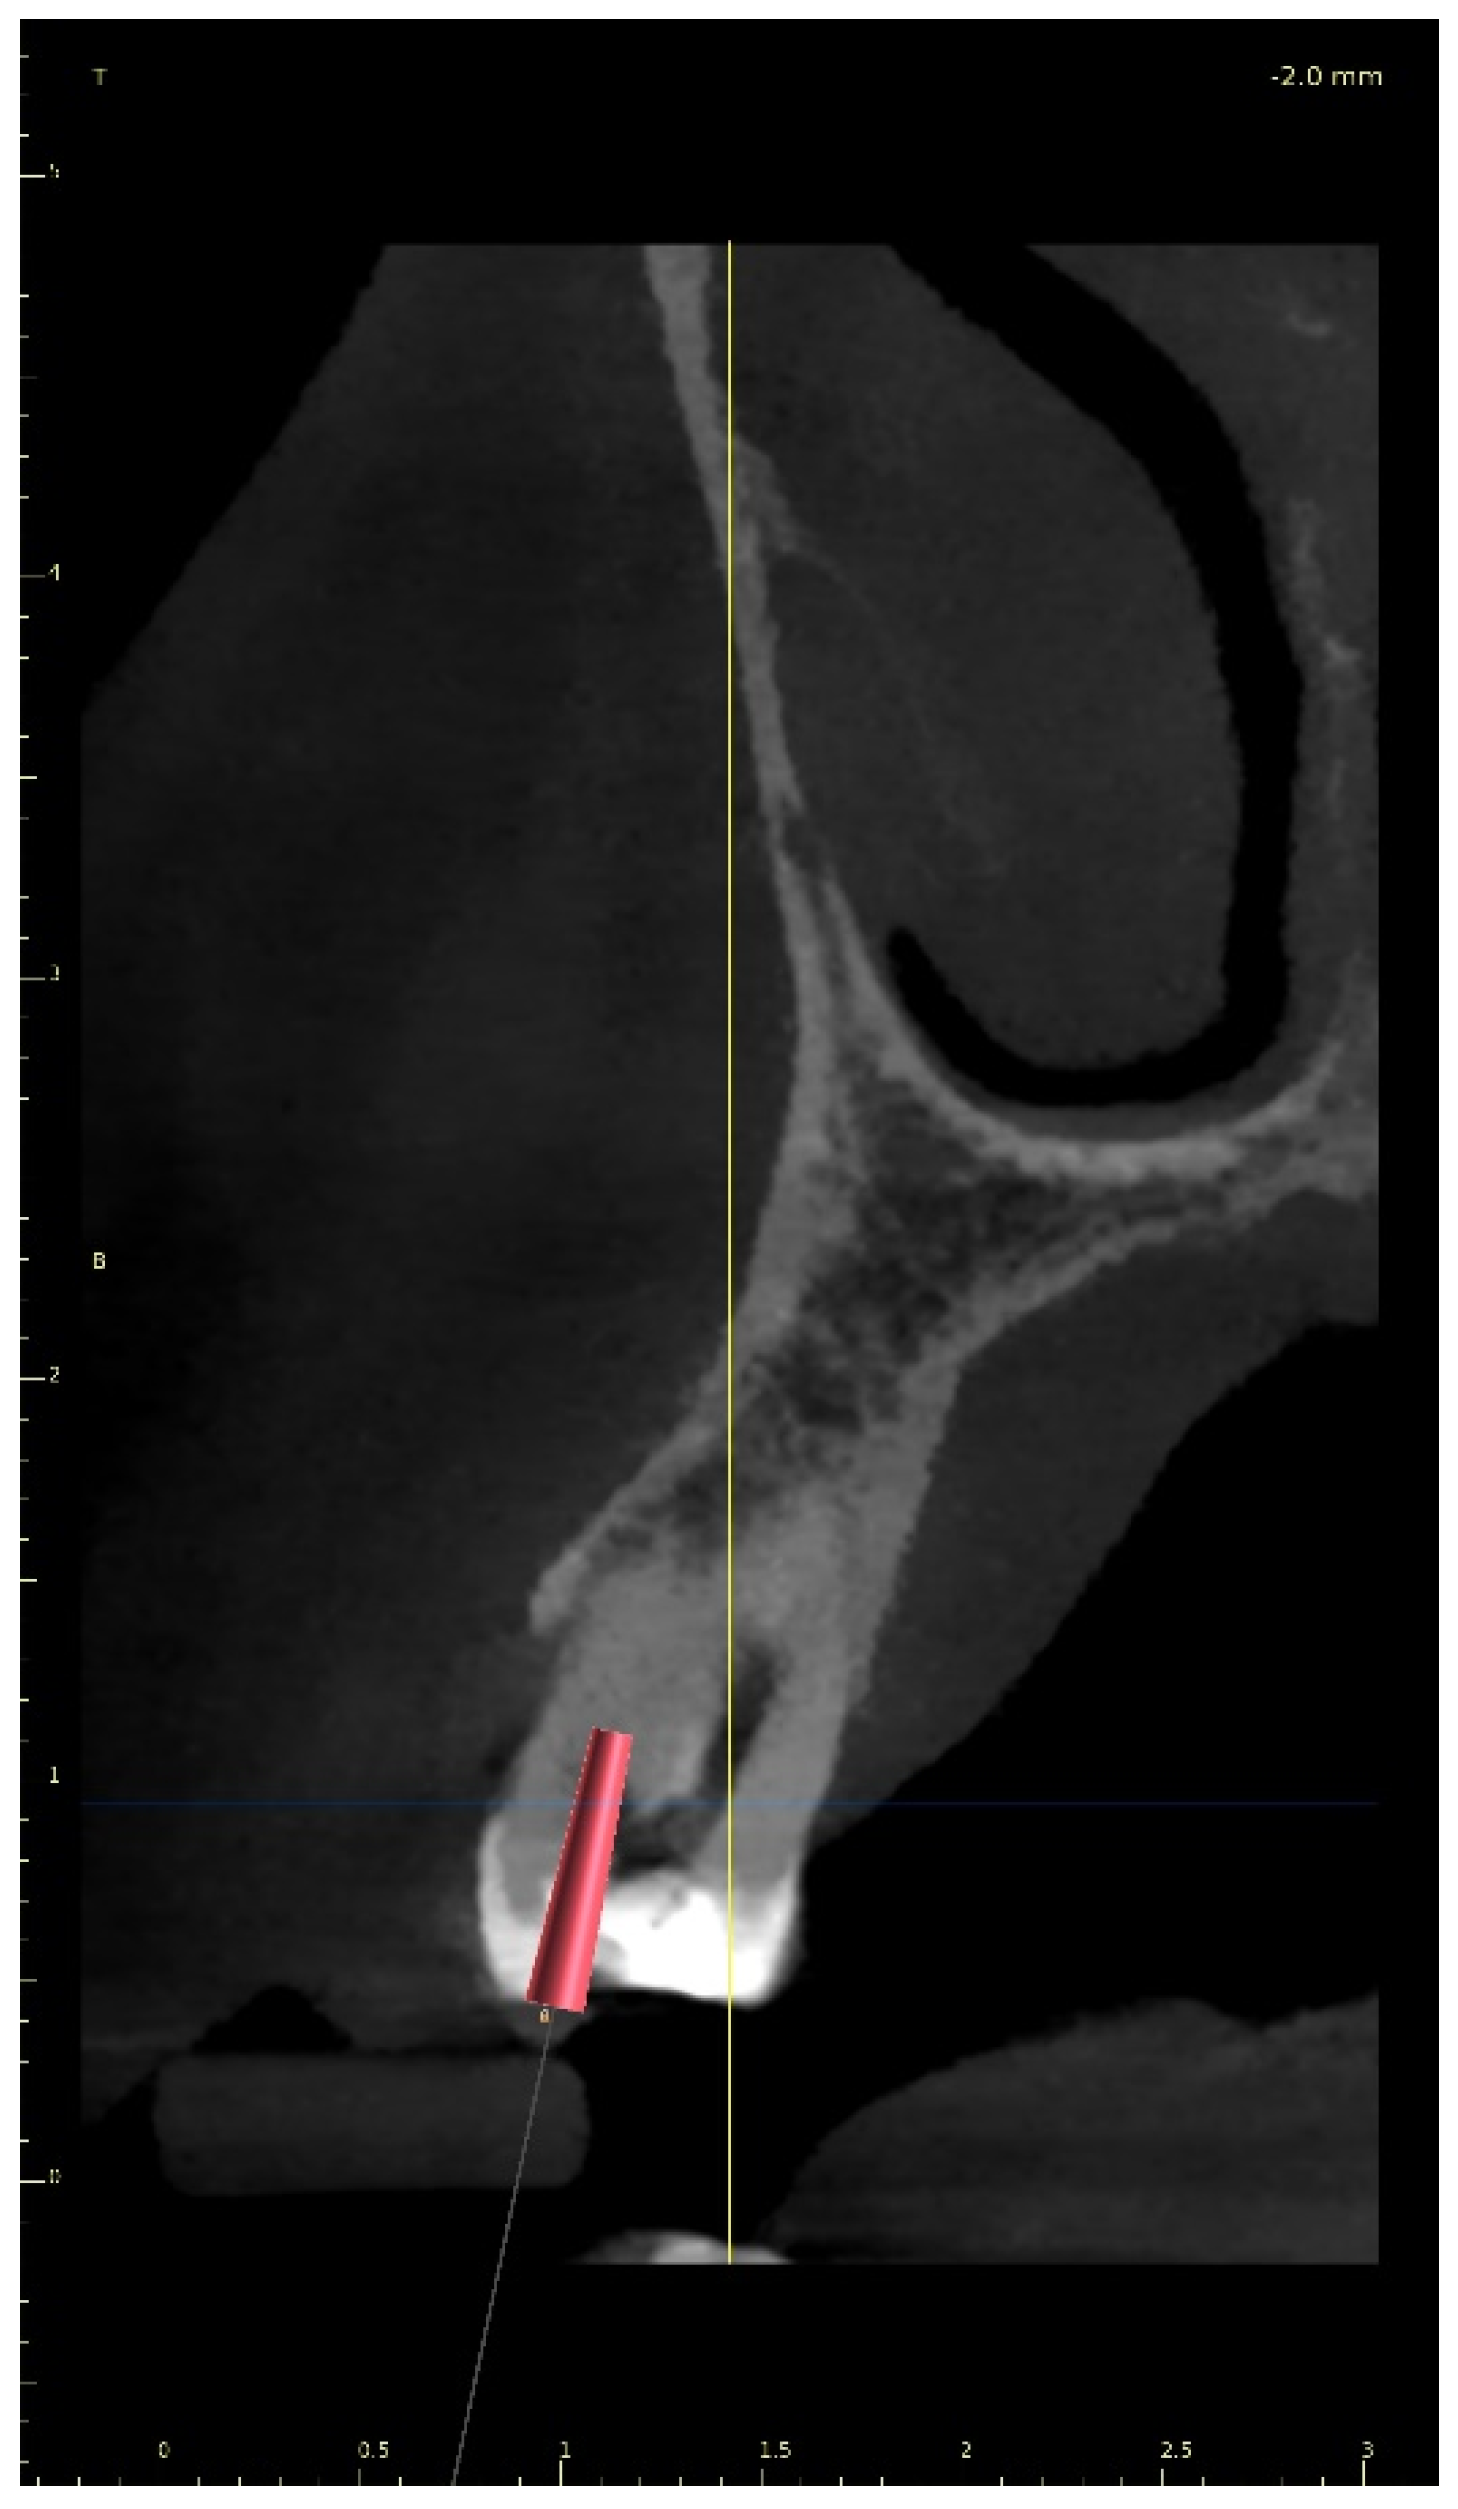

Three-Dimensional Treatment Plan

Three-Dimensional Treatment Plan and RCT